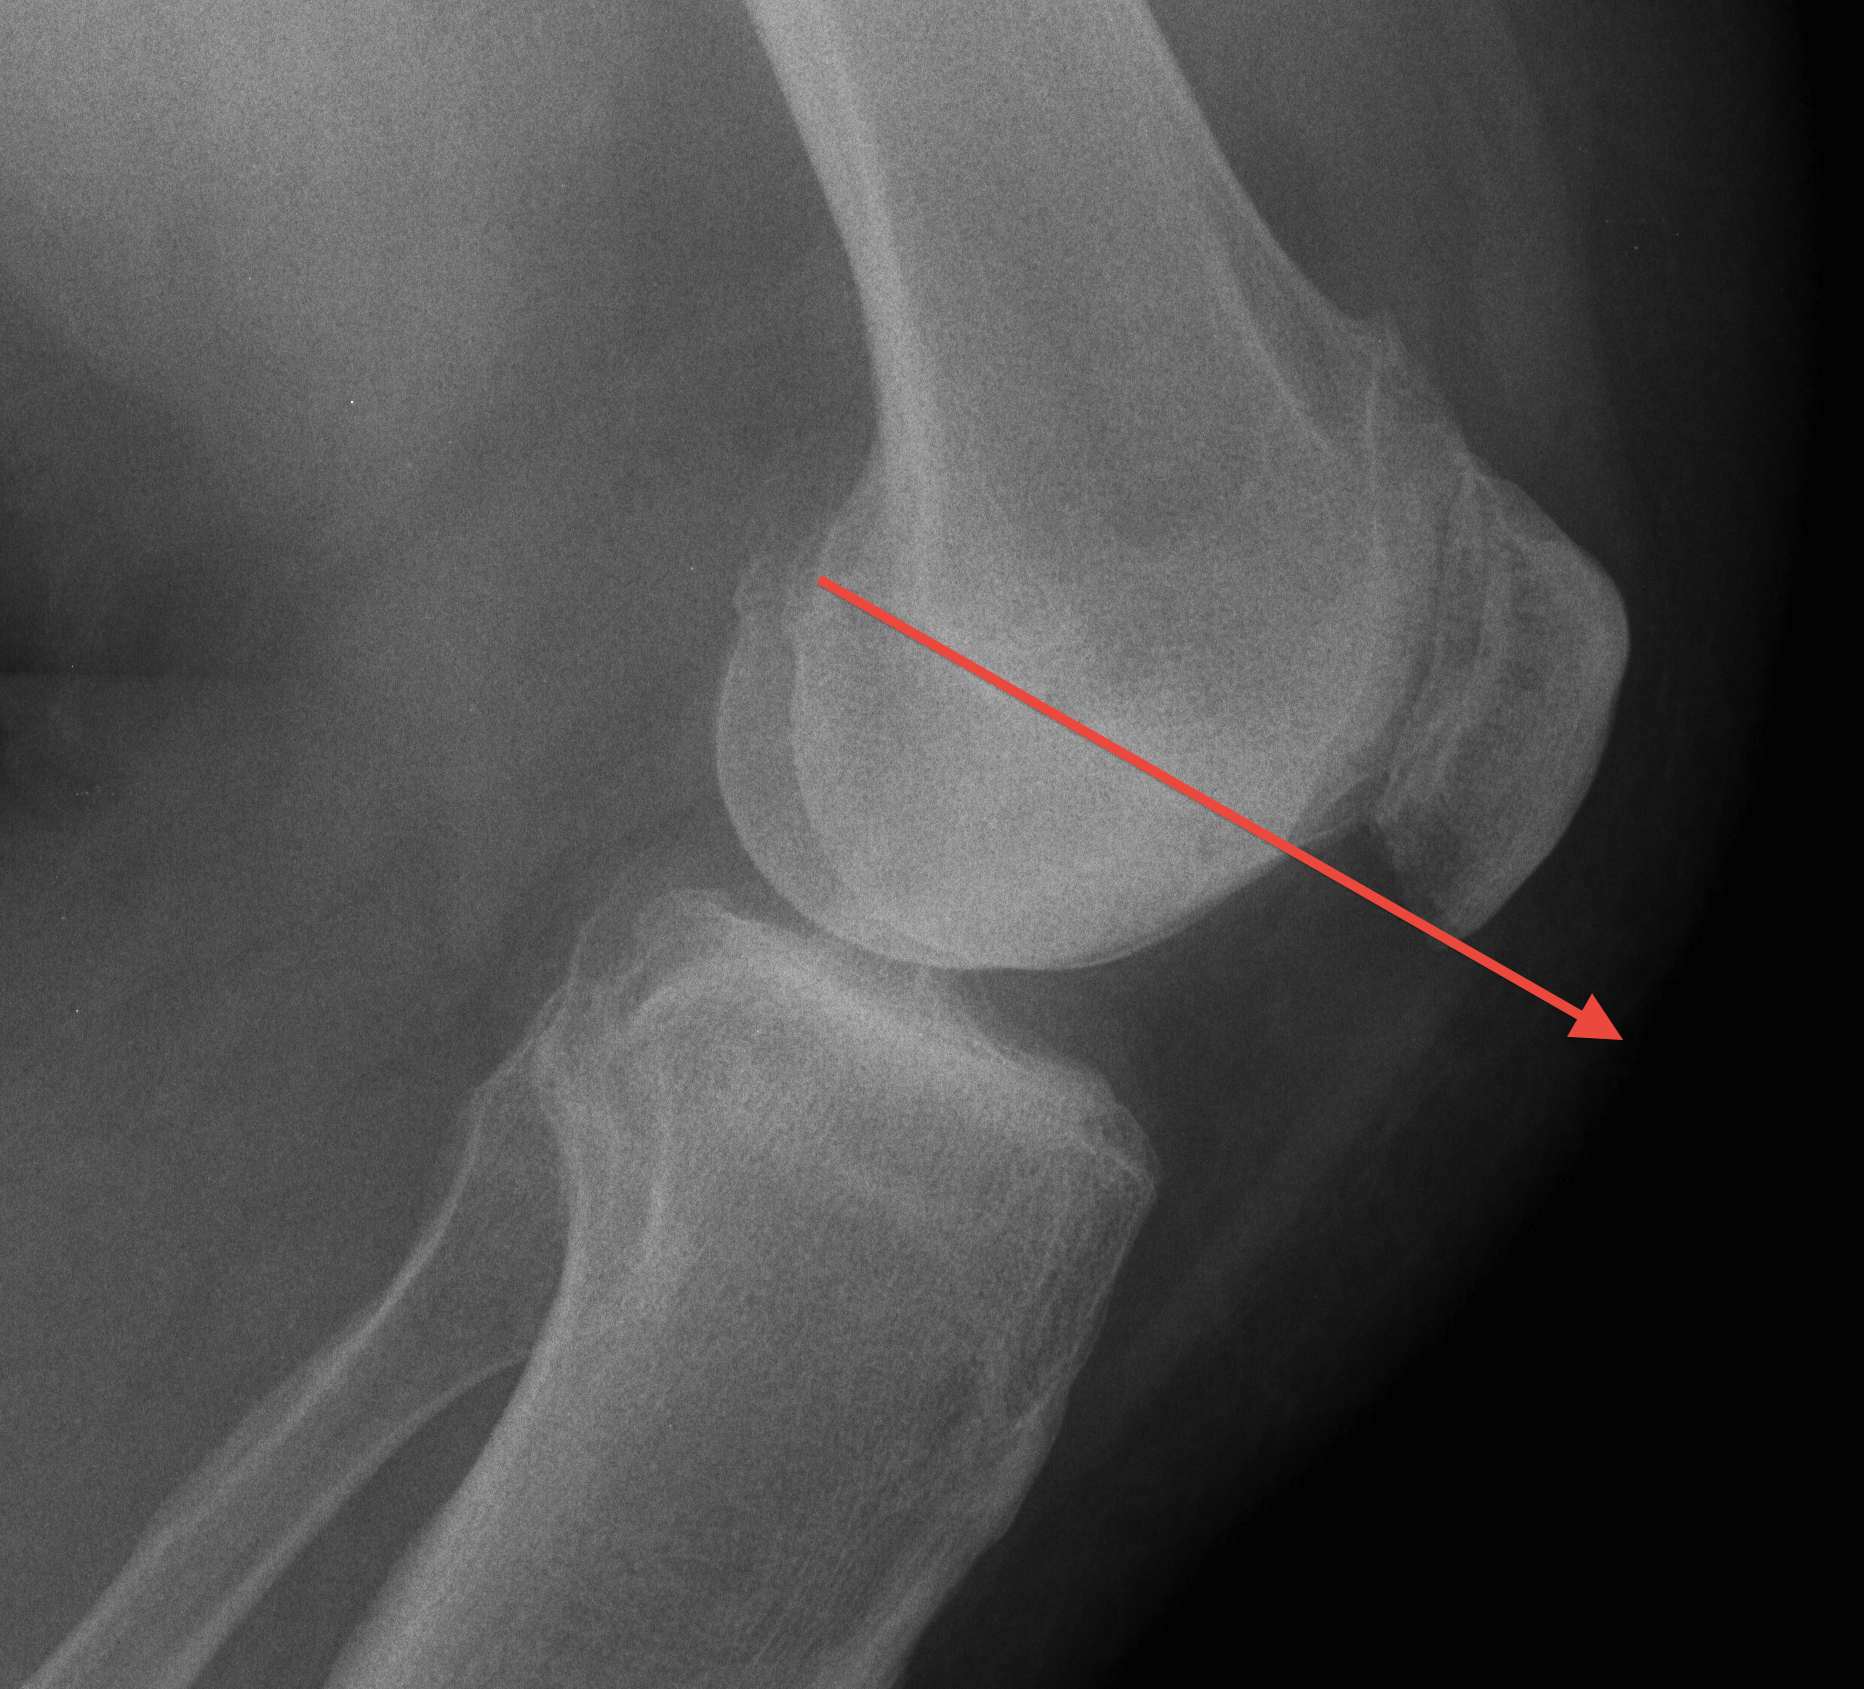

A. Blumensaat's line / Inaccurate

Knee flexed to 30o

- line should just touch inferior pole of patella

- pole above line - alta

- pole below line - baja